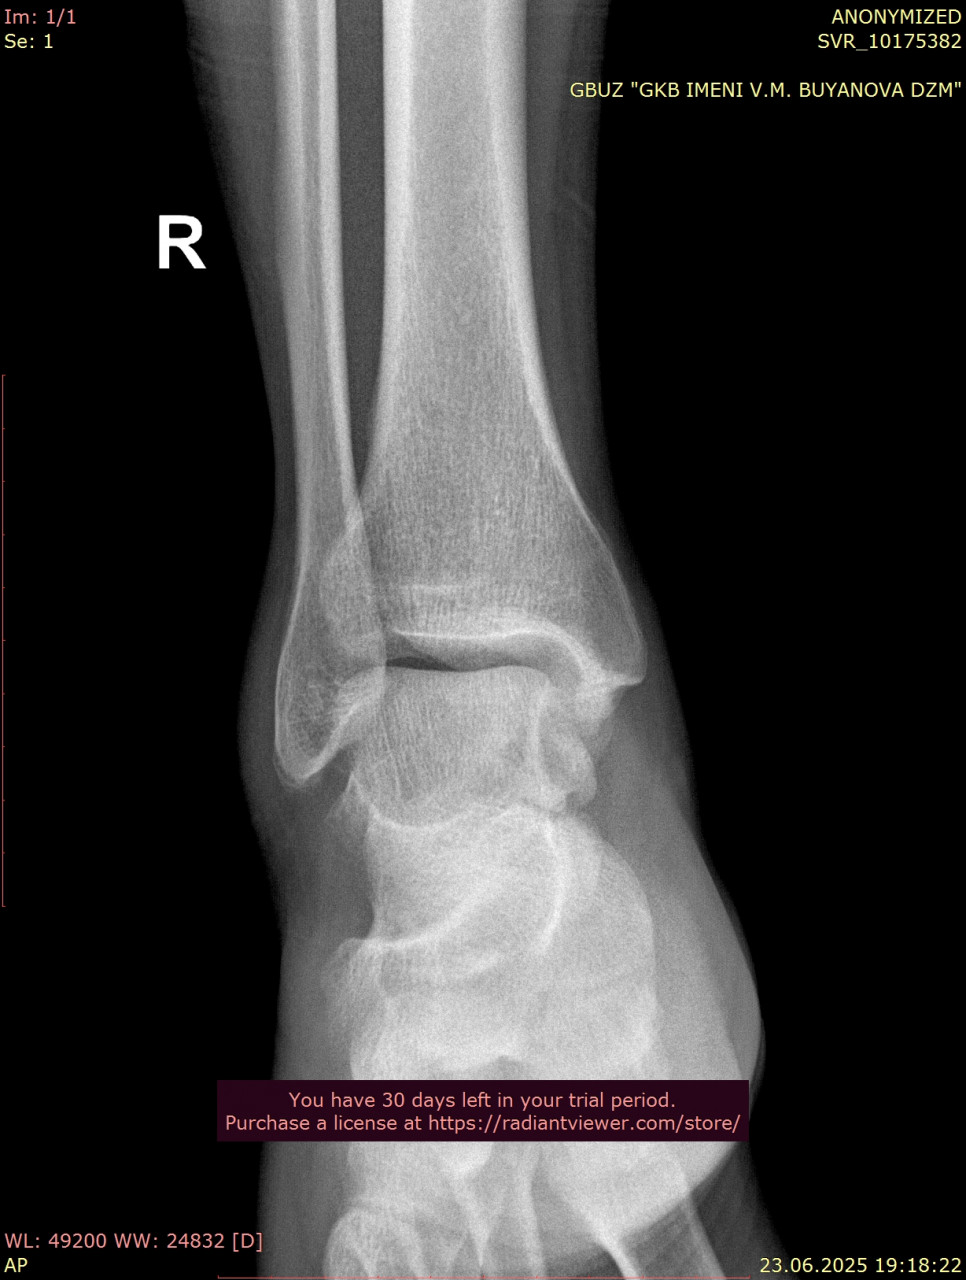

Посмотрите, пожалуйста, снимки голеностопного сустава от 23.06.2025, когда был перелом, и спустя 3 месяца от 24.09.2025. Как Вы считаете, полностью ли восстановился голеностопный сустав, артроз обязательно приведет к болям при ходьбе в ближайшие годы, можно ли этого избежать? Ведь до пенсии теперь еще далеко( Сейчас собираюсь подбирать ортопедические стельки, может посоветуете как это сделать подешевле, из за длительной нетрудоспособности денег почти нет. Смог прикрепить только одну проекцию от дыты переломаб еще есть снимки стопы, там перелом плюсневых.

Здравствуйте. На контрольных снимках костная структура выглядит восстановленной, консолидация произошла, признаков грубых осложнений нет. Артроз после таких травм возможен, но при отсутствии боли и отёка риск выраженных проблем в ближайшие годы невелик, особенно если продолжать ЛФК и постепенно наращивать нагрузку. Стельки лучше подбирать индивидуально, даже самые простые готовые варианты из аптек или ортопедических салонов могут помочь и стоят дешевле индивидуальных.